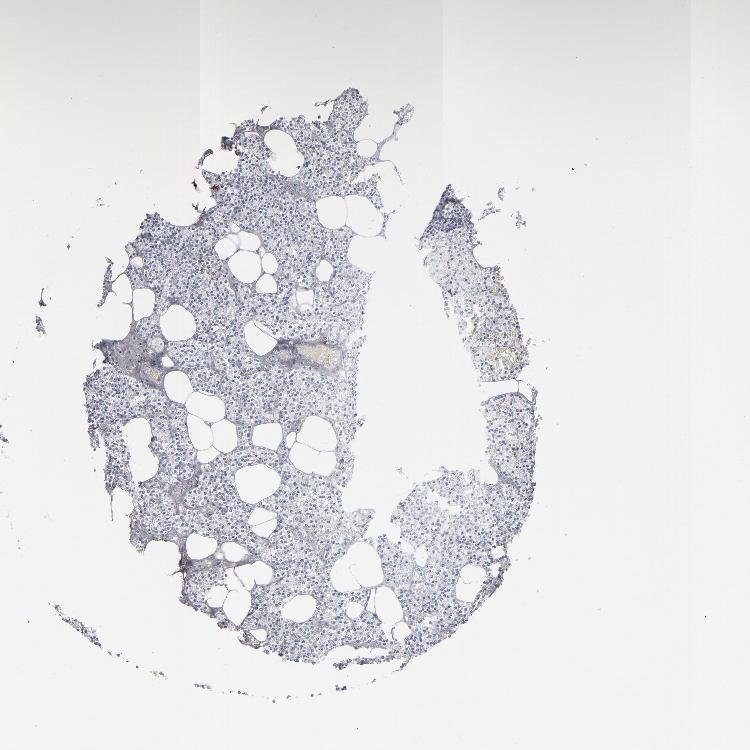

TISSUE PRIMARY DATA PARATHYROID GLAND Show tissue menu

PARATHYROID GLAND - Antibody stainingi

Antibody staining in the annotated cell types in the current human tissue is reported as not detected, low, medium, or high, based on conventional immunohistochemistry profiling in selected tissues. This score is based on the combination of the staining intensity and fraction of stained cells.

Each image is clickable and will lead to virtual microscopy that enables deeper exploration of all samples and also displays staining intensity scores, fraction scores and subcellular localization as well as patient and tissue information for each sample.

Antibody HPA002822

Glandular cells Not detected